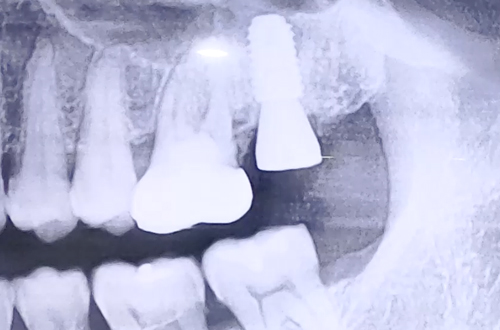

어금니 염증치료 및 발치, 임플란트 사례

왼쪽 위 큰 어금니의 통증을 호소하며 내원해 주셨던 환자분이신데, 환자분 본인도 아마도 이를 빼야 할것 같다고 말씀하실 정도의 상태이셨습니다.

가능한 자연치아를 쭉 가져가는 것이 좋으므로 자세히 검사해 보고 그 다음에 이를 빼자고 하여 엑스레이를 찍어보니 염증이 발견되었습니다.

신경치료가 되어 있던 치아이므로 치아가 건강하다면 빼지 않고 치료할 수 있으나 이가 많이 흔들리고 있어 살리기 어렵다 판단하고, 발치 후 임플란트를 계획하였습니다.

더 튼튼하고 효율적인 임플란트 치료를 위해 CT 촬영으로 염증의 위치를 정확하게 파악하는 정밀검사를 더하였고, 염증을 제거해준 뒤 비교적 튼튼히 남아있는 잇몸뼈 쪽으로 식립 후 뼈이식으로 단단히 해 드렸습니다.